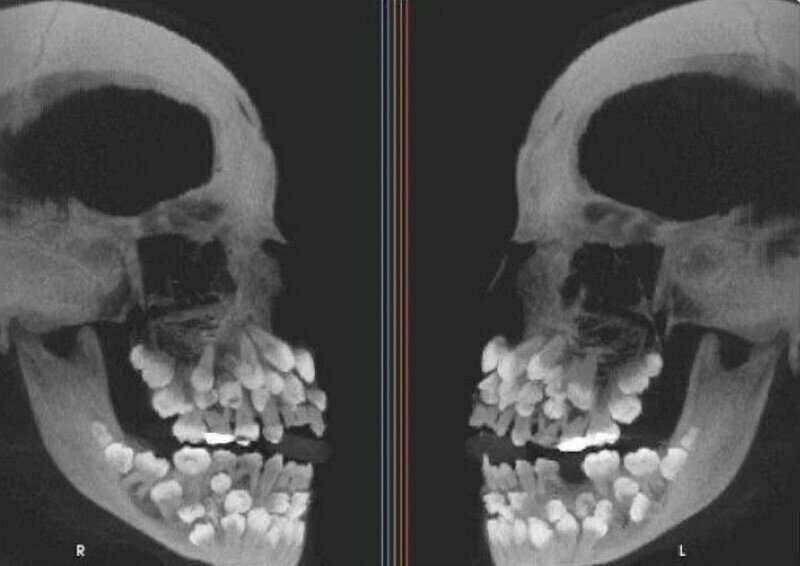

Рентген человека, больного полиодонтией, при которой вырастает аномально большое количество зубов